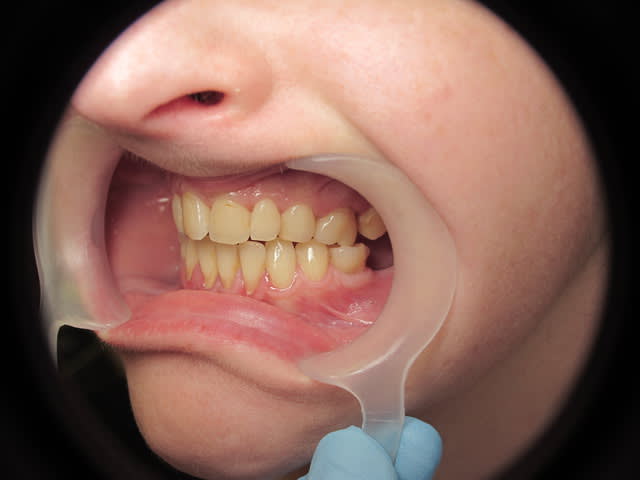

Patiente de 33 ans, questionnaire de santé RAS, demande esthétique. Elle souhaiterait que ses dents soient "davantage visibles" lors du sourire. Les dents absentes sont dues à des agénésies.

A vue de nez, je dirais qu'il y a une retroalvéolie maxillaire importante. Et je crois qu'en réalité c'est ça qui n'est pas joli.

Honnêtement, vu le nombre de prémos, d'incisives et de molaires qui manquent, je penche plutôt pour un syndrome général avec agénésies que pour des extractions ortho!

Il y a agénésies de 14-15 et 24-25, de 35 et 45 (restent 75 et 85), des molaires du bas. En haut j'avoue que je ne sais pas si ce sont des molaires de lait ou définitives...